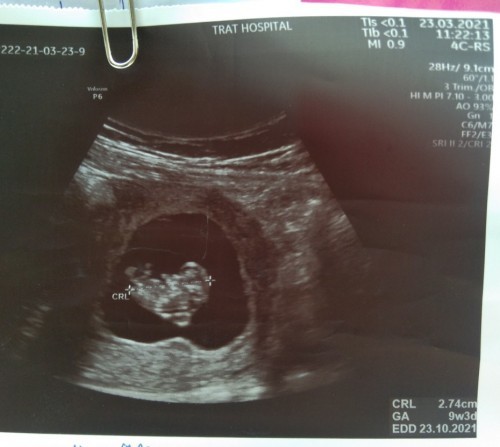

9w3dค่ะ